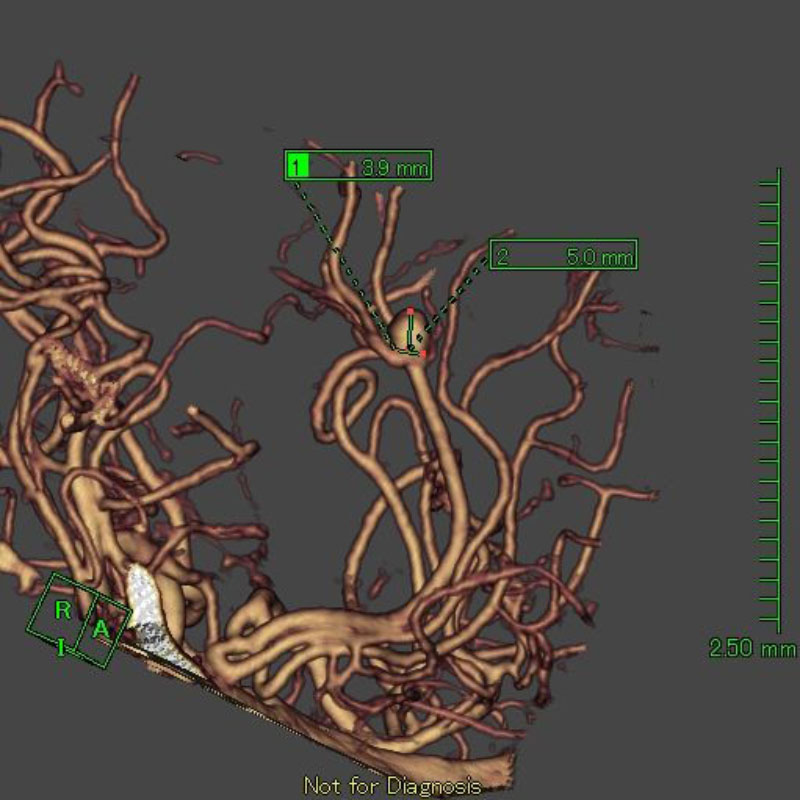

手術前

クリップ前

クリップ後

手術後

36

'25年12月

50代

左中大脳動脈瘤

クリッピング術